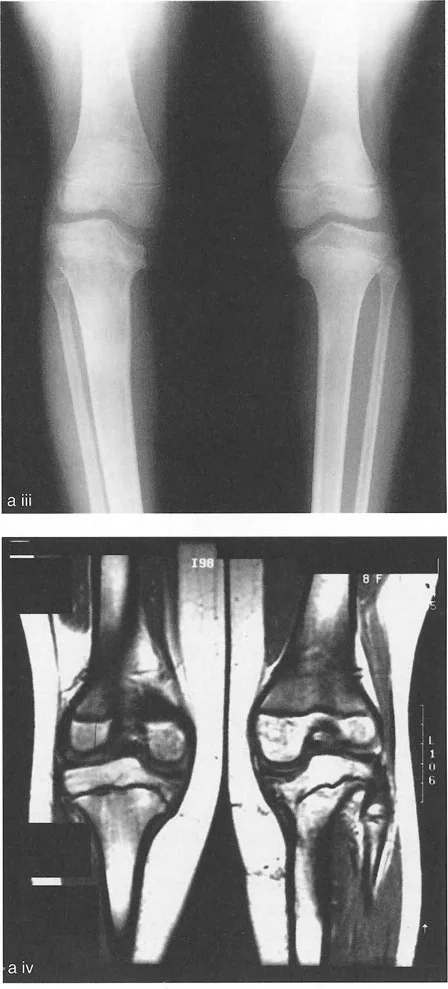

- مرض بلونت (تقوس الساق): في مرض بلونت الشديد لدى الرضع أو المراهقين، تتميز الحالة بانخفاض شديد وميل إنسي للهضبة الظنبوبية الإنسية. إذا رسمت الخطين، فإن خطي الهضبة الإنسية والوحشية يكونان بزاوية حادة بالنسبة لبعضهما البعض، ويتقاطعان بالقرب من مركز الركبة. وهذا يخلق دفعاً تقوسياً شديداً أثناء المشي.

إن المصادر المتبقية لاختلال المحاذاة تنبع من فقدان العظام والغضاريف، أو خلل التنسج الخلقي والتنموي لأسطح مفصل الركبة. السبب الأكثر شيوعاً لدى البالغين هو فقدان الغضاريف غير المتماثل من الجزء الإنسي أو الوحشي للركبة، وهو أمر نموذجي في حالات التهاب المفاصل المتقدم أو التنكس ما بعد الصدمة. أما لدى الأطفال، فتسيطر حالات مثل مرض بلونت أو توقف نمو صفيحة النمو.

عندما يفقد الغضروف بشكل غير متماثل - كما هو الحال في التهاب المفاصل الكلاسيكي في الجزء الإنسي من الركبة - أو عندما تنخفض الهضبة الظنبوبية جسدياً بسبب صدمة عالية الطاقة أو مرض نمائي، تفقد هذه الخطوط المفصلية علاقتها المتوازية. التأثير البيوميكانيكي هو زيادة مرضية في الزاوية التوافقية لخط المفصل. كلما زادت هذه الزاوية، تتضاعف قوى القص عبر المفصل، مما يسرع المزيد من تدهور الغضروف ويزيد من انحراف المحور الميكانيكي.